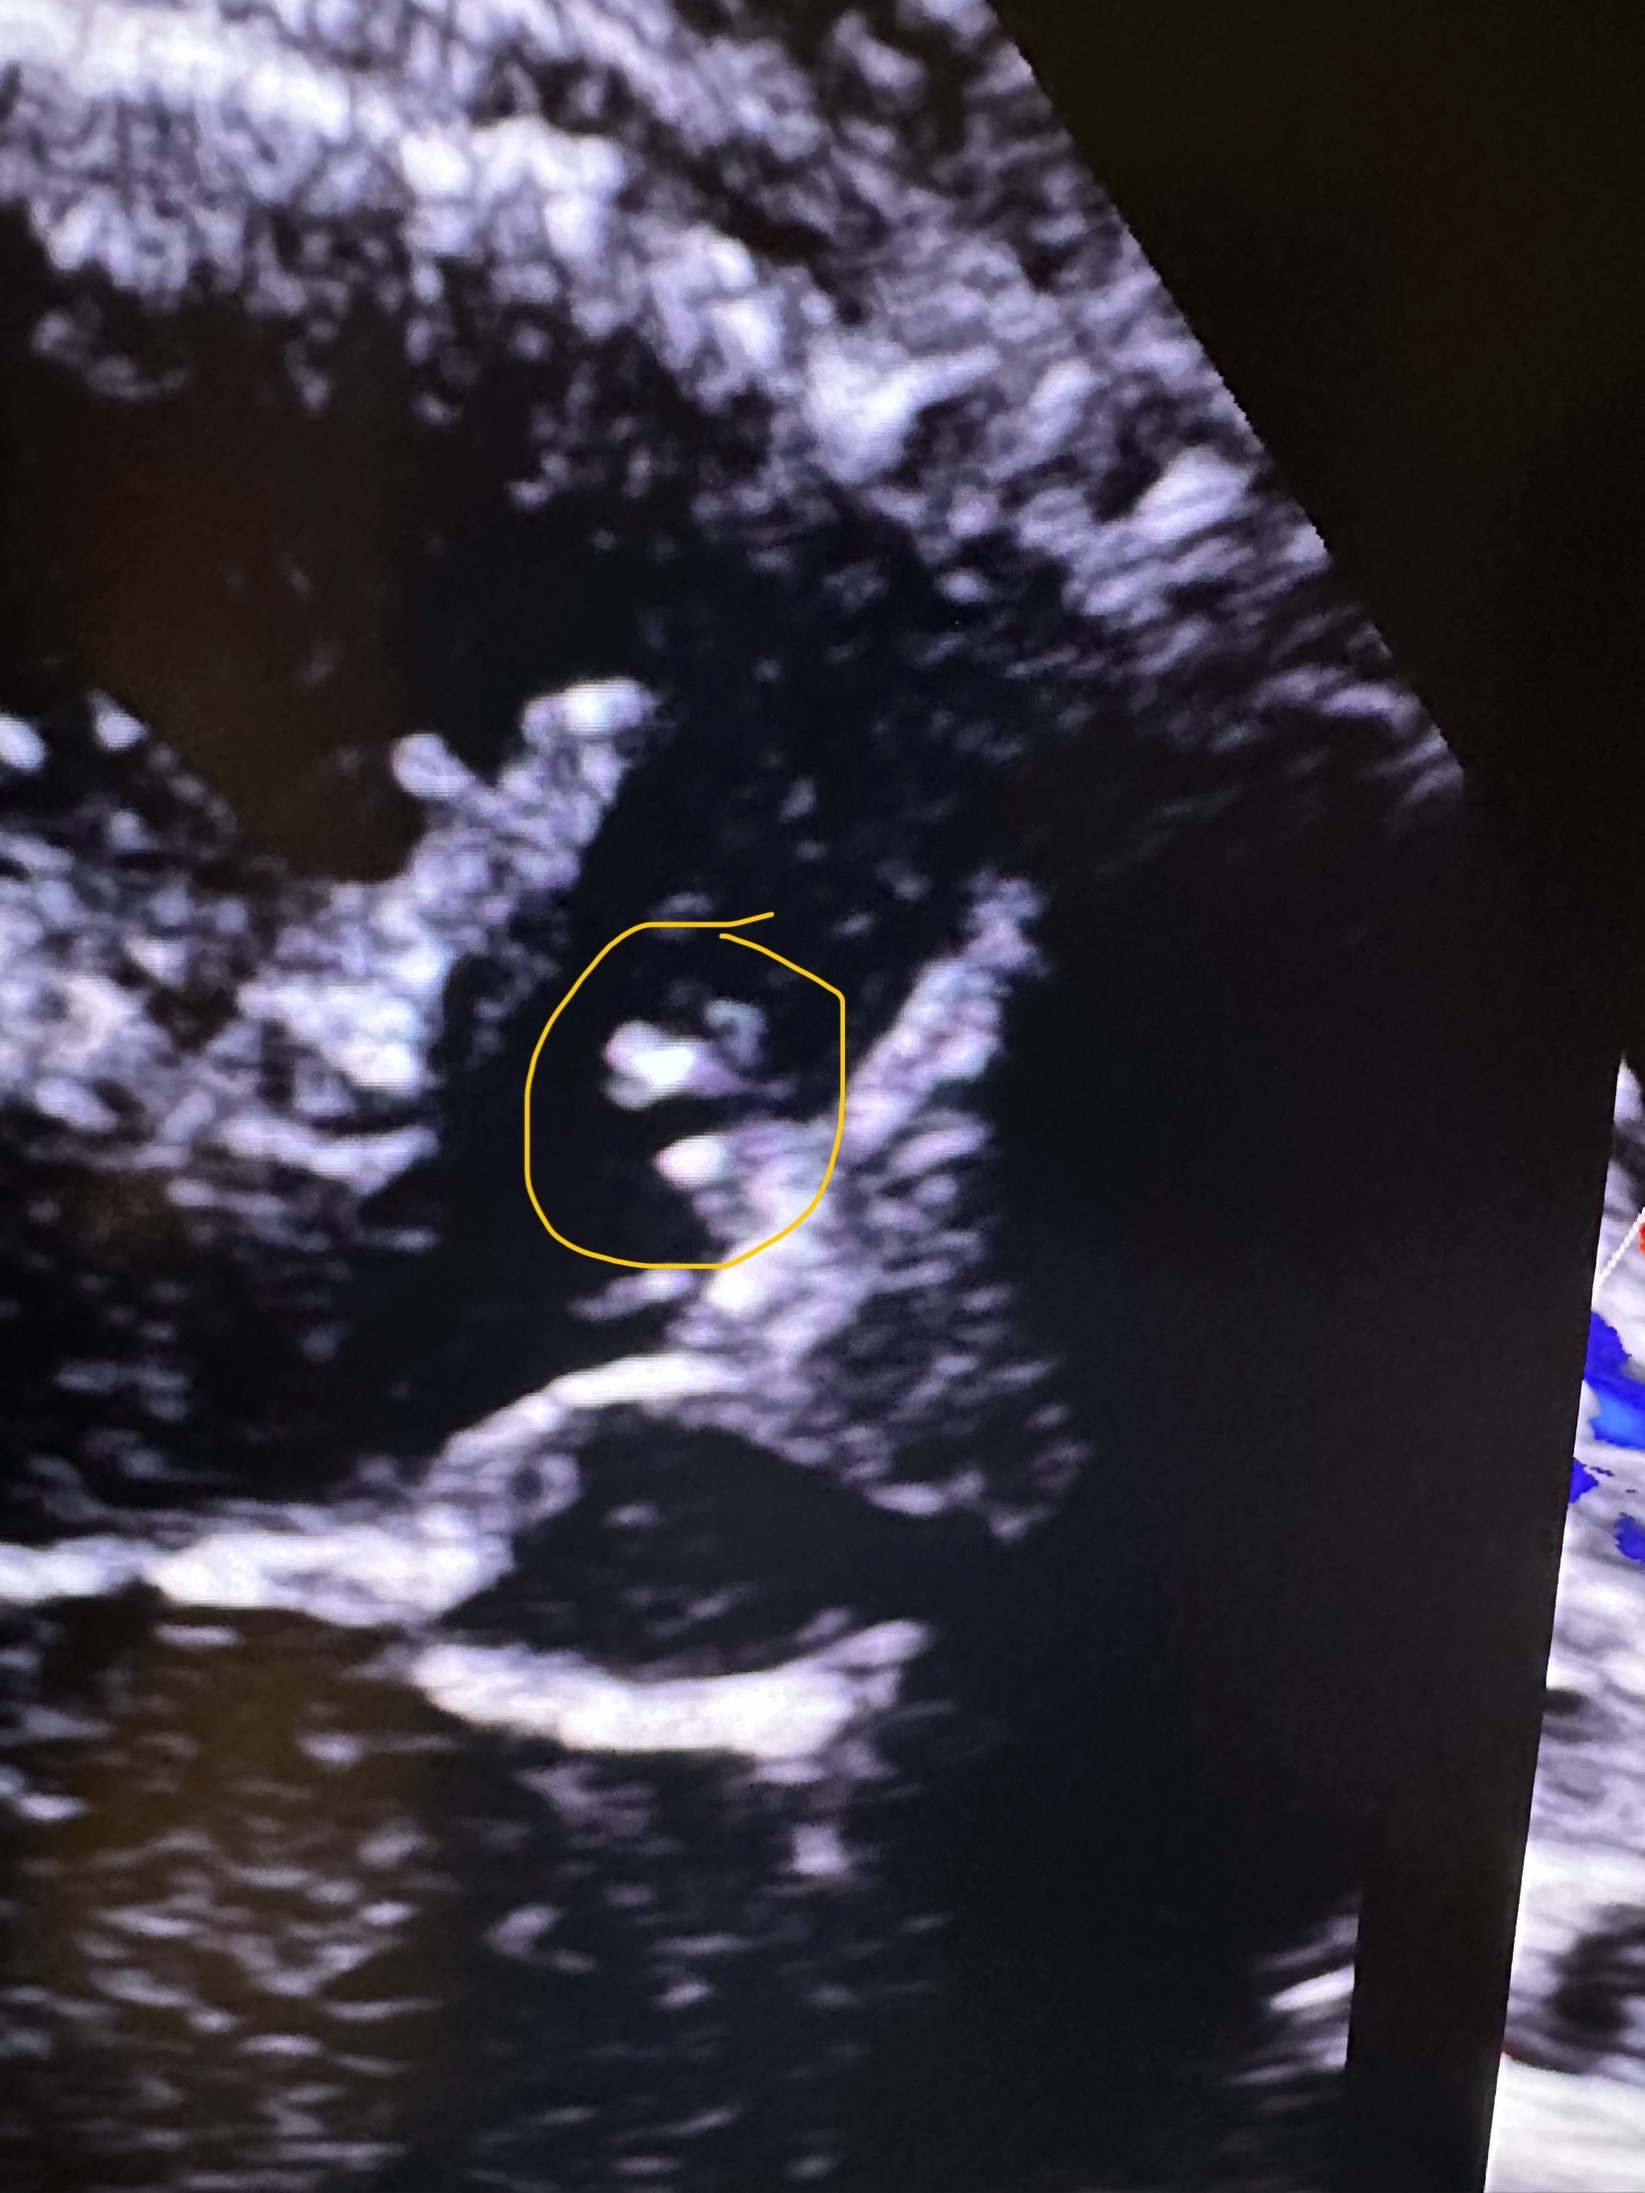

I’m raising funds for my dear friend Renae’s family. Their brave little girl, Maddyn, will be facing open-heart surgery due to VSD (ventricular septal defect), a form of congenital heart disease (CHD).